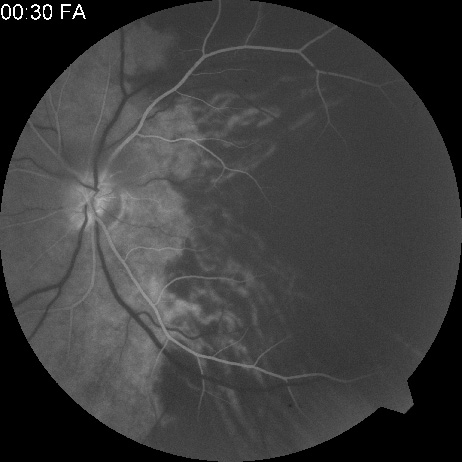

Obstruction of one of the posterior ciliary arteries may result in a whitening of the area of the retina supplied by the involved posterior ciliary artery and the subsequent appearance of patchy pigmentation in the same area. However, in patients with anterior ischemic optic neuropathy secondary to temporal arteritis the retina may appear normal (Fig. 5). In the case of either the medial posterior ciliary artery or the lateral posterior ciliary artery, the area involved is the size of approximately half of the choroid.121–123 In the case of a long posterior ciliary artery, the temporal side of the eye including the macula is involved.121

Fig. 5. A: Ischemic optic neuropathy in a patient with giant cell arteritis. B and C: Intravenous fluorescein angiography demonstrates delayed filling of the lateral posterior ciliary artery.

We have seen several patients with anterior ischemic optic neuropathy with suspected temporal arteritis where the Westergren sedimentation rate and C-reactive protein were normal and the intravenous fluorescein angiogram helped confirm the diagnosis (Fig. 5).